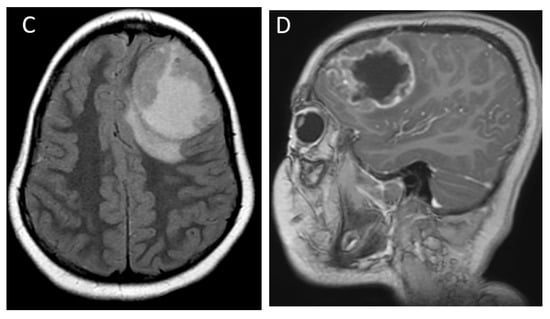

| Medulloblastoma | Exclusively posterior fossa Most commonly in fourth ventricle/cerebellar vermis (non-WNT, non-SHH, or WNT), can involve cerebellopontine angle (WNT) or cerebellar hemispheres with extra-axial extension (SHH) | Diffusion restricting Variable enhancement Cystic/necrotic change may be present Calcifications uncommon Taurine peak characteristic |

| Atypical teratoid/rhabdoid tumor | Posterior fossa (slightly more common) or cerebral hemispheres May be extra-axial | Diffusion restricting Enhancement usually present More heterogenous than medulloblastomas, with cysts/necrosis, calcification, and hemorrhage |

| Supratentorial embryonal | Cerebral hemispheres or deep nuclei, rarely intraventricular | Large tumor Diffusion restricting solid components Variable cysts/necrosis and hemorrhage |